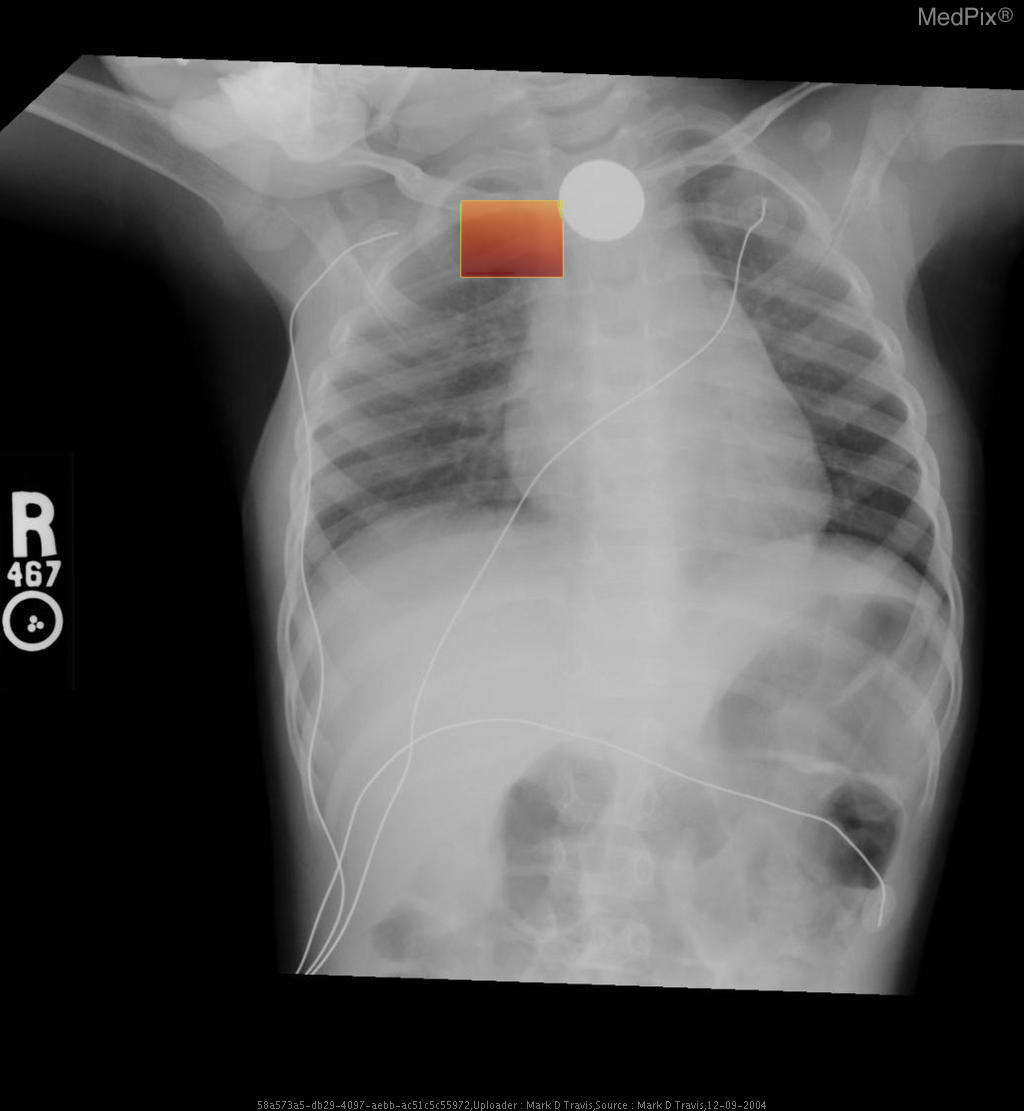

Esophageal foreign body - Coin ingestion

- Frontal chest and upper abdominal X-ray with standard orientation (image-left = patient-right).

- A well-circumscribed, round metallic density (coin) projects over the upper thoracic midline, posterior to the tracheal air column — typical of an object lodged in the esophagus rather than the trachea.

- No evidence of significant tracheal narrowing, suggesting airway is patent.

- Lung fields are clear bilaterally; no focal consolidation, effusion, or pneumothorax detected.

- Cardiothoracic ratio within normal range for age.

- Normal diaphragmatic contour and position; no subdiaphragmatic free air visualized.

- Enteric and monitoring tubes appear appropriately placed without complication.

2) Most likely diagnosis and why:

Esophageal foreign body (coin) lodged in the upper esophagus. The round metallic opacity centered over the thoracic midline and seen full-face on AP view indicates an esophageal (not tracheal) location—since tracheal foreign bodies appear more radiolucent and typically lie off-midline or show edge-on orientation. The absence of significant respiratory compromise supports esophageal lodging. Context consistency: Consistent — matches the provided context of “coin ingestion” in a pediatric patient. Confidence: 95%

3) Next best diagnostic step:

Immediate clinical evaluation for airway stability is essential. If stable, proceed with a lateral neck/chest radiograph to confirm the anteroposterior position of the coin and exclude airway involvement. Endoscopic removal should be arranged urgently if the coin is confirmed within the upper esophagus, given aspiration and mucosal injury risk.

4) Key differential or confirmatory test:

A lateral chest or neck X-ray is the key confirmatory test — differentiating esophageal (flat, face-on coin) from tracheal (edge-on coin) position. If uncertainty persists, an upper endoscopy (rigid or flexible) provides definitive localization and allows immediate retrieval.

5) Possible treatment or management:

** Emergency management involves keeping the child NPO and arranging removal under sedation or general anesthesia. Endoscopic extraction is the preferred and safe technique. Post-removal inspection of the esophageal mucosa for ulceration or stricture formation is essential. Additional imaging may be needed if perforation, aspiration, or secondary complications are suspected.